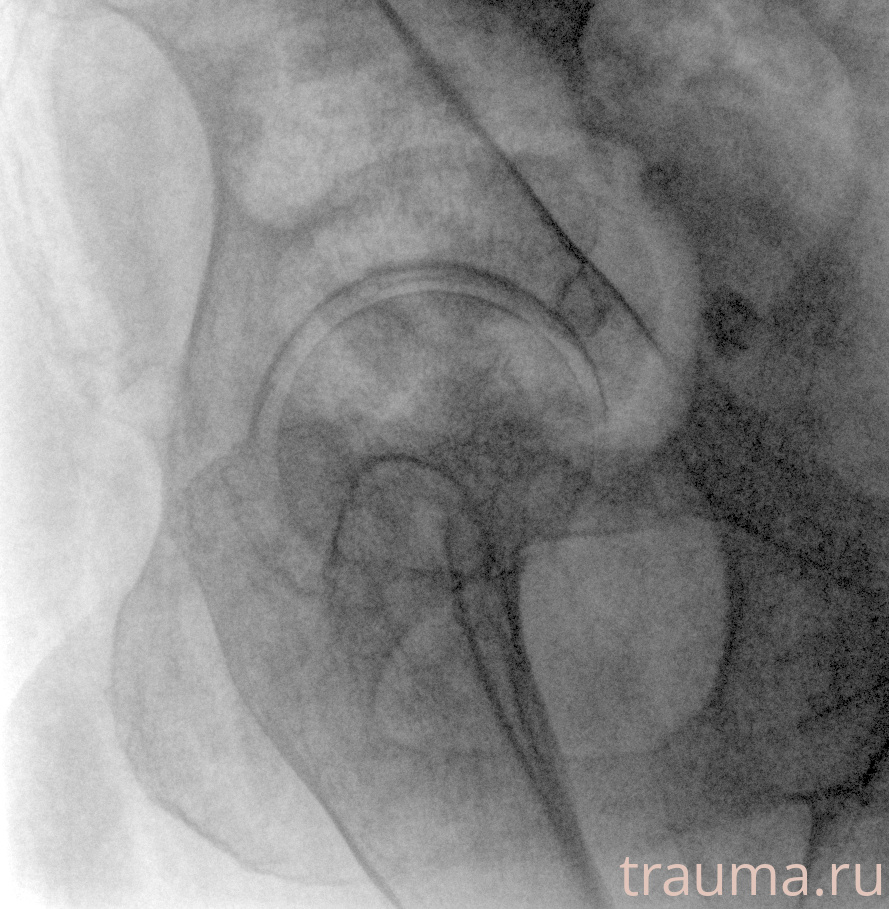

Рентгенограммы

Рентген на дому: по вашему адресу приезжает врач-рентгенолог, травматолог-ортопед с мобильным рентгеновским аппаратом, проводит диагностику травмы или заболевания, делает необходимые рентгенограммы, дает рекомендации по дальнейшему лечению. Получить качественные снимки в домашних условиях возможно благодаря уникальной методике, разработанной МосРентген Центром для института  Склифосовского